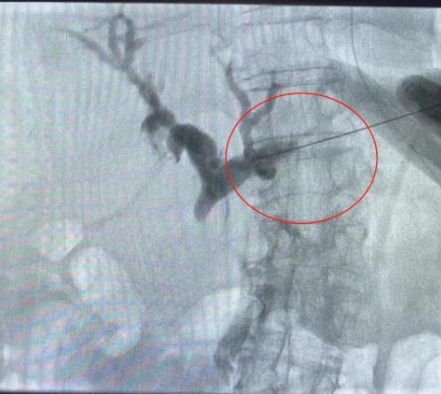

由于患者肝右葉占位巨大,完全遮擋右側(cè)穿刺路徑,左肝管為唯一穿刺路徑。介入科彭鵬醫(yī)生與重癥醫(yī)學(xué)科討論后,征得患者家屬同意后,擬行左側(cè)經(jīng)皮肝內(nèi)膽管穿刺引流術(shù)。術(shù)中一針便成功進(jìn)入膽道系統(tǒng),導(dǎo)絲引流管放置順利,造影顯示膽道系統(tǒng)顯影滿意,側(cè)孔位置可,引流順暢,37分鐘便結(jié)束了手術(shù),術(shù)后順利轉(zhuǎn)入普外科護(hù)理治療。這例手術(shù)的成功開展,刷新了該院介入團(tuán)隊(duì)高齡患者手術(shù)的新記錄!

經(jīng)皮肝內(nèi)膽管穿刺引流術(shù)是在醫(yī)學(xué)影像的引導(dǎo)下,利用穿刺針經(jīng)皮穿入肝內(nèi)膽管,注入對比劑,使肝內(nèi)外膽管迅速顯影后,置管引流以緩解梗阻癥狀。對于惡性梗阻性黃疸患者,通過該方式可降低血清膽紅素,有助于恢復(fù)肝腎功能,提高其生存質(zhì)量,延長生存期,部分患者還可獲得進(jìn)一步治療的機(jī)會。對于良性梗阻性黃疸患者,除有利于迅速緩解黃疸和感染等癥狀外,還可為后續(xù)治療提供通道。